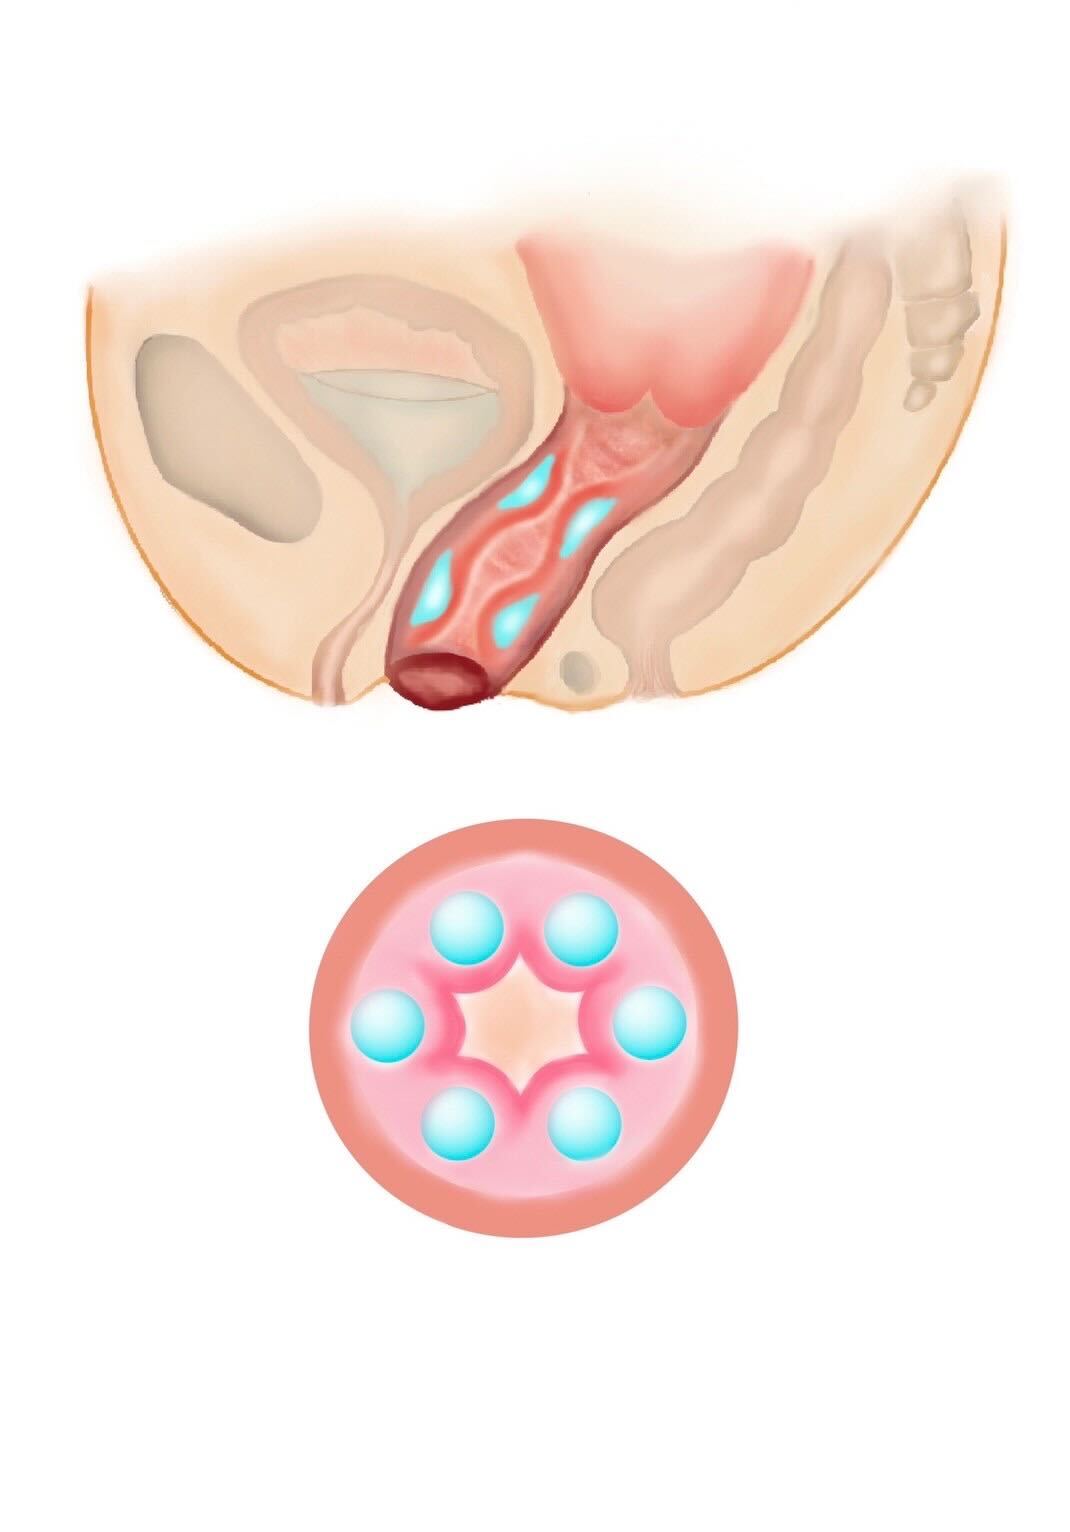

Type02

たこつぼ

② 円周注入(膣の締まり感向上)

膣の周囲に均等に注入し、膣壁にボリュームをもたせる方法で、膣粘膜のハリを高め、膣のフィット感を向上させる可能性があります。

出産後に膣のゆるみを感じる方、膣のハリ不足が気になる方に適しています。

また、ご希望に応じて、巾着、タコつぼ、数の子天井、俵締め、みみず千匹などと称される施術方法にも対応しております。